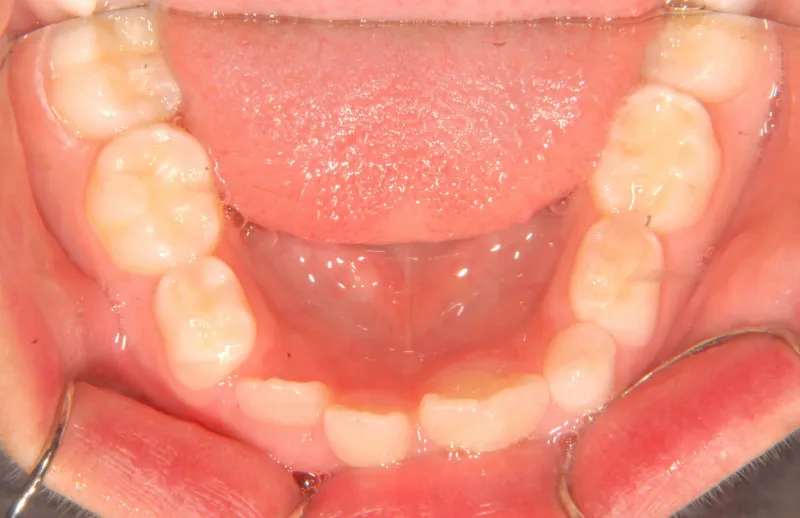

初診時年齢 小学校2年生 (男性) 主訴 癒合歯・永久歯が生えるスペースがない

診断名 叢生 装置名

状態 永久歯が生える隙間がない(叢生)

ガタガタ・でこぼこに生えている(叢生)

上下の歯並びが狭く、永久歯の生える隙間がありません。

右下に癒合歯があり 上下の歯並びのアーチが悪くなっています。